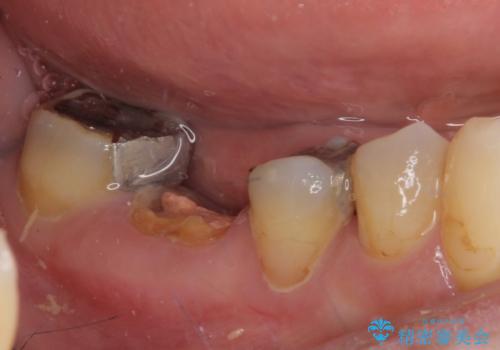

- 他院で、抜歯してインプラント補綴するしかないとのことで来院された患者様です。

診査したところ、抜歯と診断された歯は、他院での診断通り抜歯が必要でした。

ただし、インプラント以外にブリッジでの補綴治療も可能であったので、抜歯後に治癒を待って、フルジルコニアブリッジにて補綴することとしました。